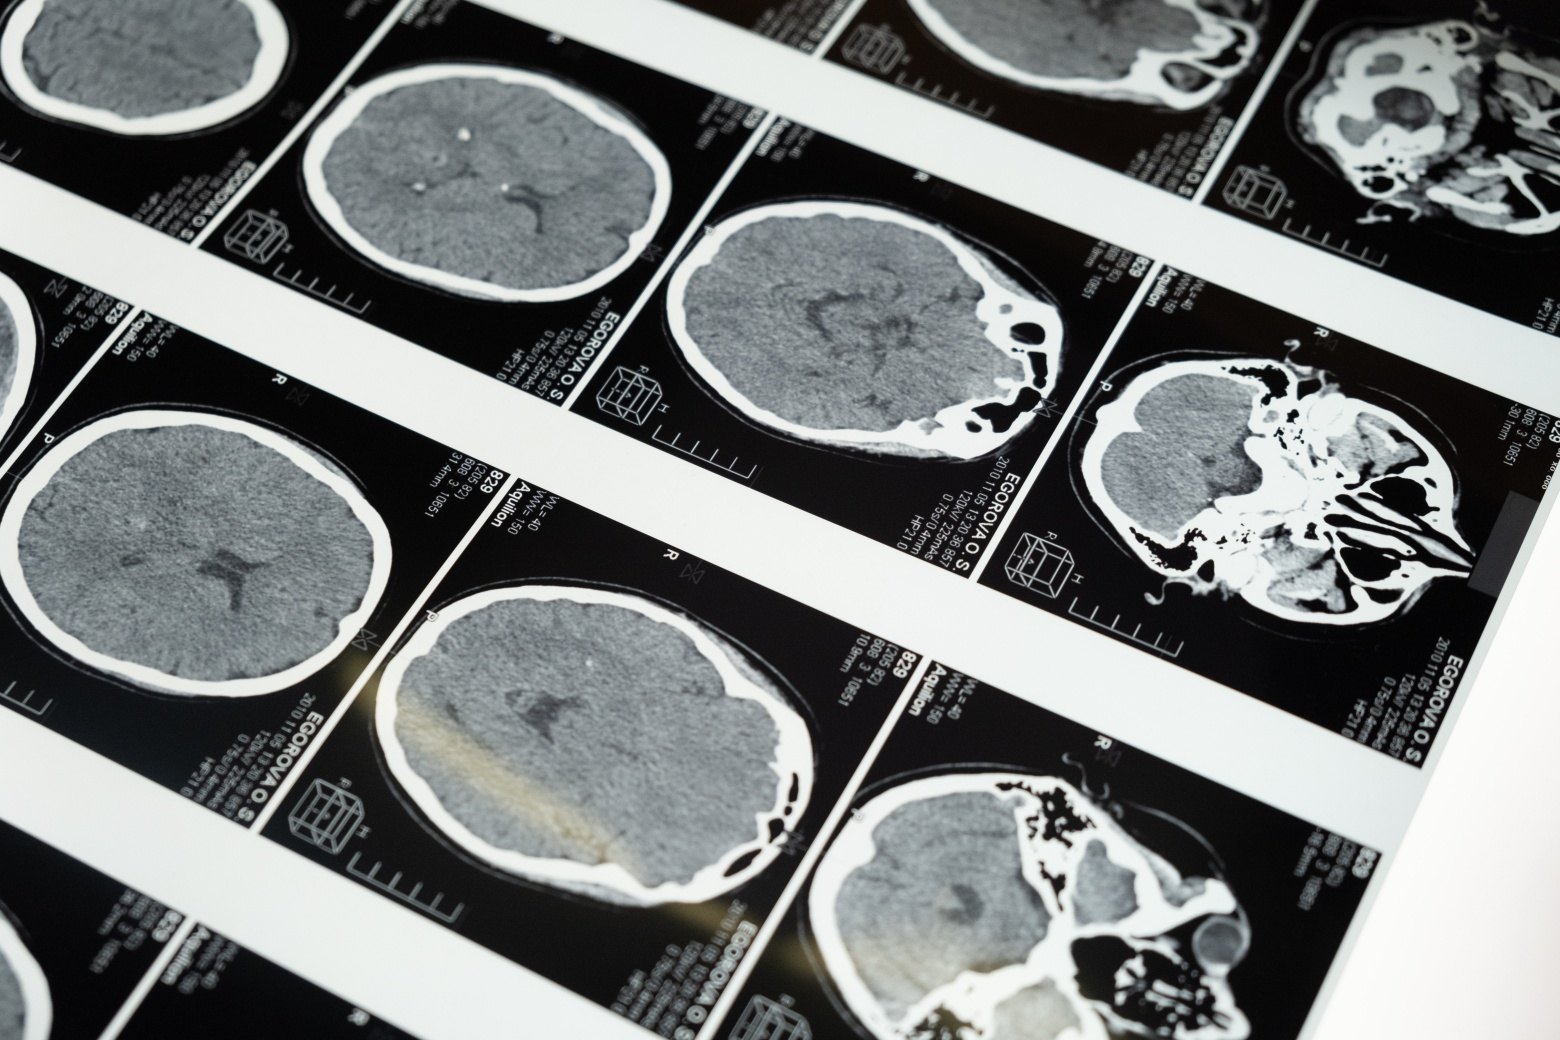

치료방법

1. 허혈성: 응고 분해 약 또는 혈액 시너를 투여하는 방법이 있고 뇌경색 예방을 위한 아스피린도 투여가 가능합니다.

2. 출혈성: 뇌압을 낮추기 위한 약을 투여하는데 심한 경우 과잉 혈액을 제거하기 위한 수술을 진행할 수도 있고 파열된 혈관치료를 위해 수술을 하기도 합니다.